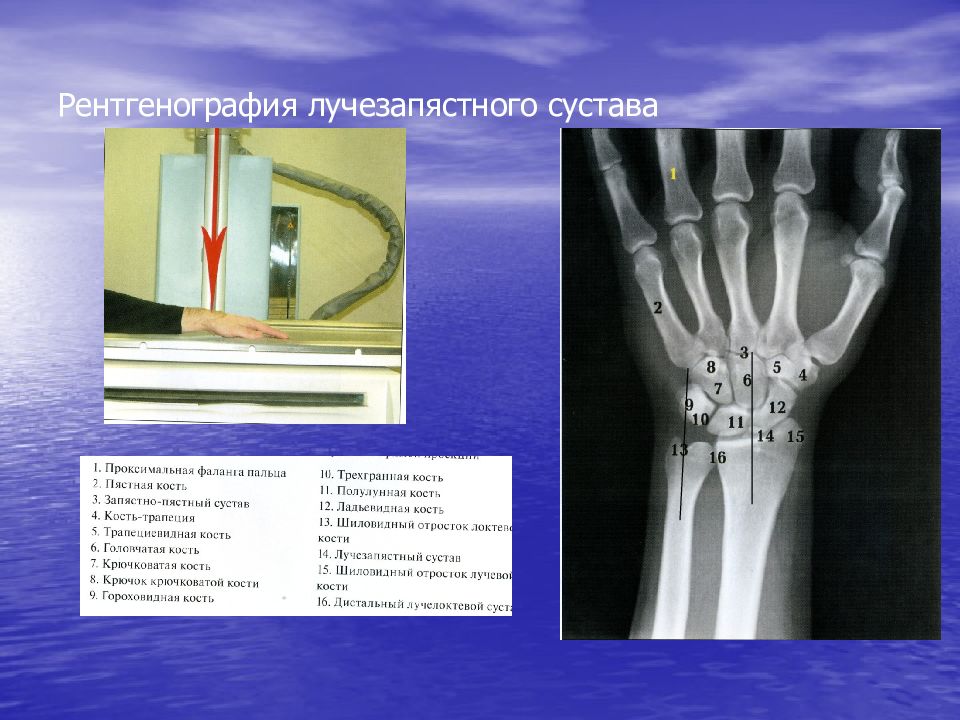

Подборка рентгеновских снимков лучезапястного сустава